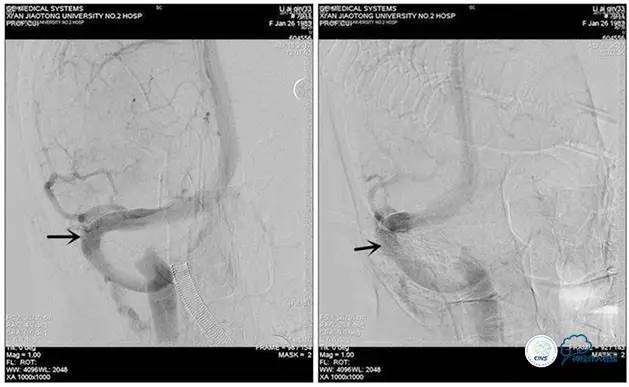

诊疗方案:为挽救视力,确定支架成形术效果,急诊行右侧横窦乙状窦狭窄球囊扩张术(6mm×20mm,Ever Cross )。

术中测压

远端压力:530mmH2O

近端压力:120mmH2O

术中造影

术后造影

狭窄较前有改善

术中测压:

远端:520mmH2O,

近端:190mmH2O。

治疗方案:

1、8mm×40mm , EverCross球囊扩张;

2、8mm×40mm,Protégé自膨支架成形术。

术后右侧ICA造影

术后远、近端压力差为:0